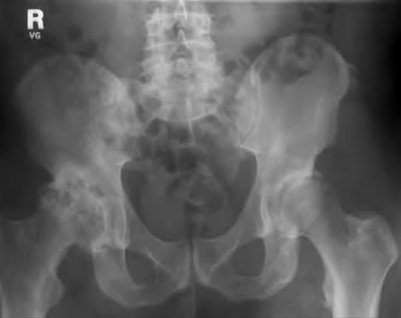

A 65-year-old woman with painful knee arthritis and the deformity seen in Figure A, is scheduled to undergo a total knee arthroplasty. All the following are risk factors for a post-operative peroneal palsy EXCEPT:

The clinical presentation is consistent with end-stage arthritis in a valgus knee. All of the factors listed are risk factors for peroneal nerve palsy EXCEPT female gender, which is not a risk factor.

Figure A demonstrates and AP radiograph of the knee showing end-stage arthritis with severe lateral compartment narrowing.